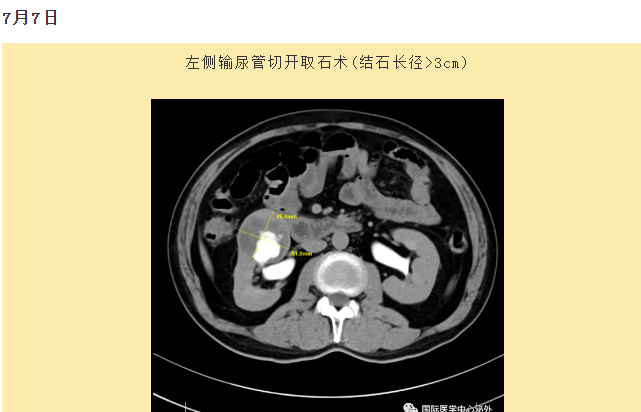

西安國際醫(yī)學(xué)中心醫(yī)院順利完成了達(dá)芬奇Xi(第四代)機(jī)器人裝機(jī)。7月6日—7月15日,泌尿外科成功完成了達(dá)芬奇Xi(第四代)機(jī)器人手術(shù)6例,標(biāo)志著科室微創(chuàng)外科邁入新時代,造福萬千患者。